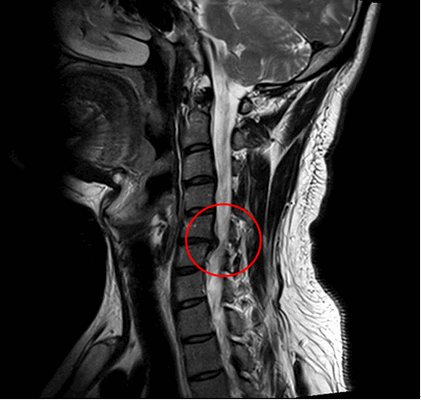

МРТ шейного отдела позвоночника: множественные дегенеративные изменения межпозвонковых дисков шейного отдела позвоночника. Дегенеративный стеноз позвоночного канала на уровне С4-С5, С5-С6, С6-С7. Левосторонняя префораминальная протрузия диска С5-С6. Правосторонняя парамедианная протрузия диска С6-С7. Спондилоартроз 2 степени. Фораминальный стеноз С3-С4 С6-С7 с двух сторон, С4-С5 С5-С6 слева.

Пациенту был поставлен диагноз: распространенный остеохондроз шейного, грудного и поясничного отделов позвоночника. Дегенеративный стеноз позвоночного канала на уровне С6-С7 справа. Формирующийся артифициальный костно-металлический блок на уровне Th10-L1 после транспедикулярной фиксации. Формирующийся артифициальный костно-металлический блок на уровне L4-L5, L5-S1 после транспедикулярной фиксации и заднего межтелового спондилодеза. Компрессионно-ишемическая радикулопатия С7 справа. Выраженный болевой синдром.

Была проведена операция: тотальная дискэктомия С5-С6, С6-С7, микрохирургическая декомпрессия спинного мозга и его корешков, вентральный межтеловой спондилодез имплантатом из пористого никелида титана.